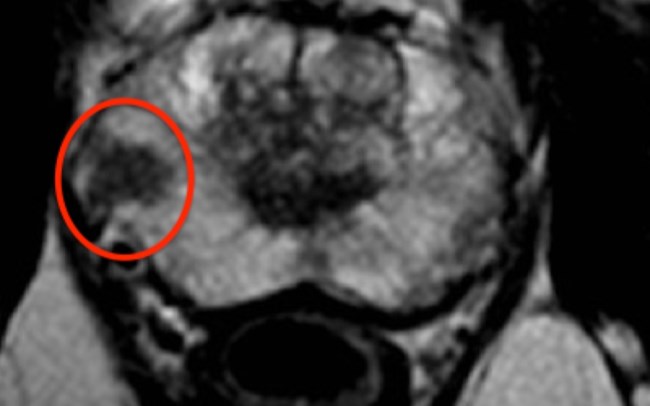

Όταν το PSA ή/και η Δακτυλική εξέταση (ΔΕΠ) θέτουν τέτοιες υπόνοιες, ο ασθενής χρήζει μιας ειδικής μαγνητικής, την Πολυπαραμετική Μαγνητική Τομογραφία Προστάτη. Αυτή αποτελεί τη μοναδική απεικονιστική εξέταση που μπορεί να ανιχνεύσει κλινικά σημαντική εστία καρκίνου προστάτη ακόμα και διαμέτρου λίγων χιλιοστών.

Με οδηγό την πολυπαραμετρική μαγνητική, θα ακολουθήσει η Βιοψία προστάτη. Αυτή θα πρέπει να λαμβάνεται όχι μόνο από κάθε περιοχή του προστάτη, αλλά και στοχευμένα από την ύποπτη περιοχή που υποδεικνύει η μαγνητική (σύστημα fusion).

- Την εξονυχιστική μελέτη της πολυπαραμετρικής μαγνητικής τομογραφίας του προστάτη σε συνδυασμό με την τοπογραφία των θετικών βιοψιών (όρια του όγκου από την κάψα, νόσος σε περισσότερες εστίες και πού στον προστάτη, απόσταση του καρκίνου από τα αγγειονευρώδη δεμάτια του προστάτη υπεύθυνα για τη στύση κλπ)-λογισμικό του ρομπότ